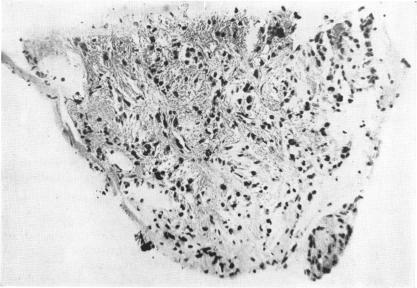

Intraocular biopsy: an evaluation.

Trans Am Ophthalmol Soc. 1952;50:375-405.